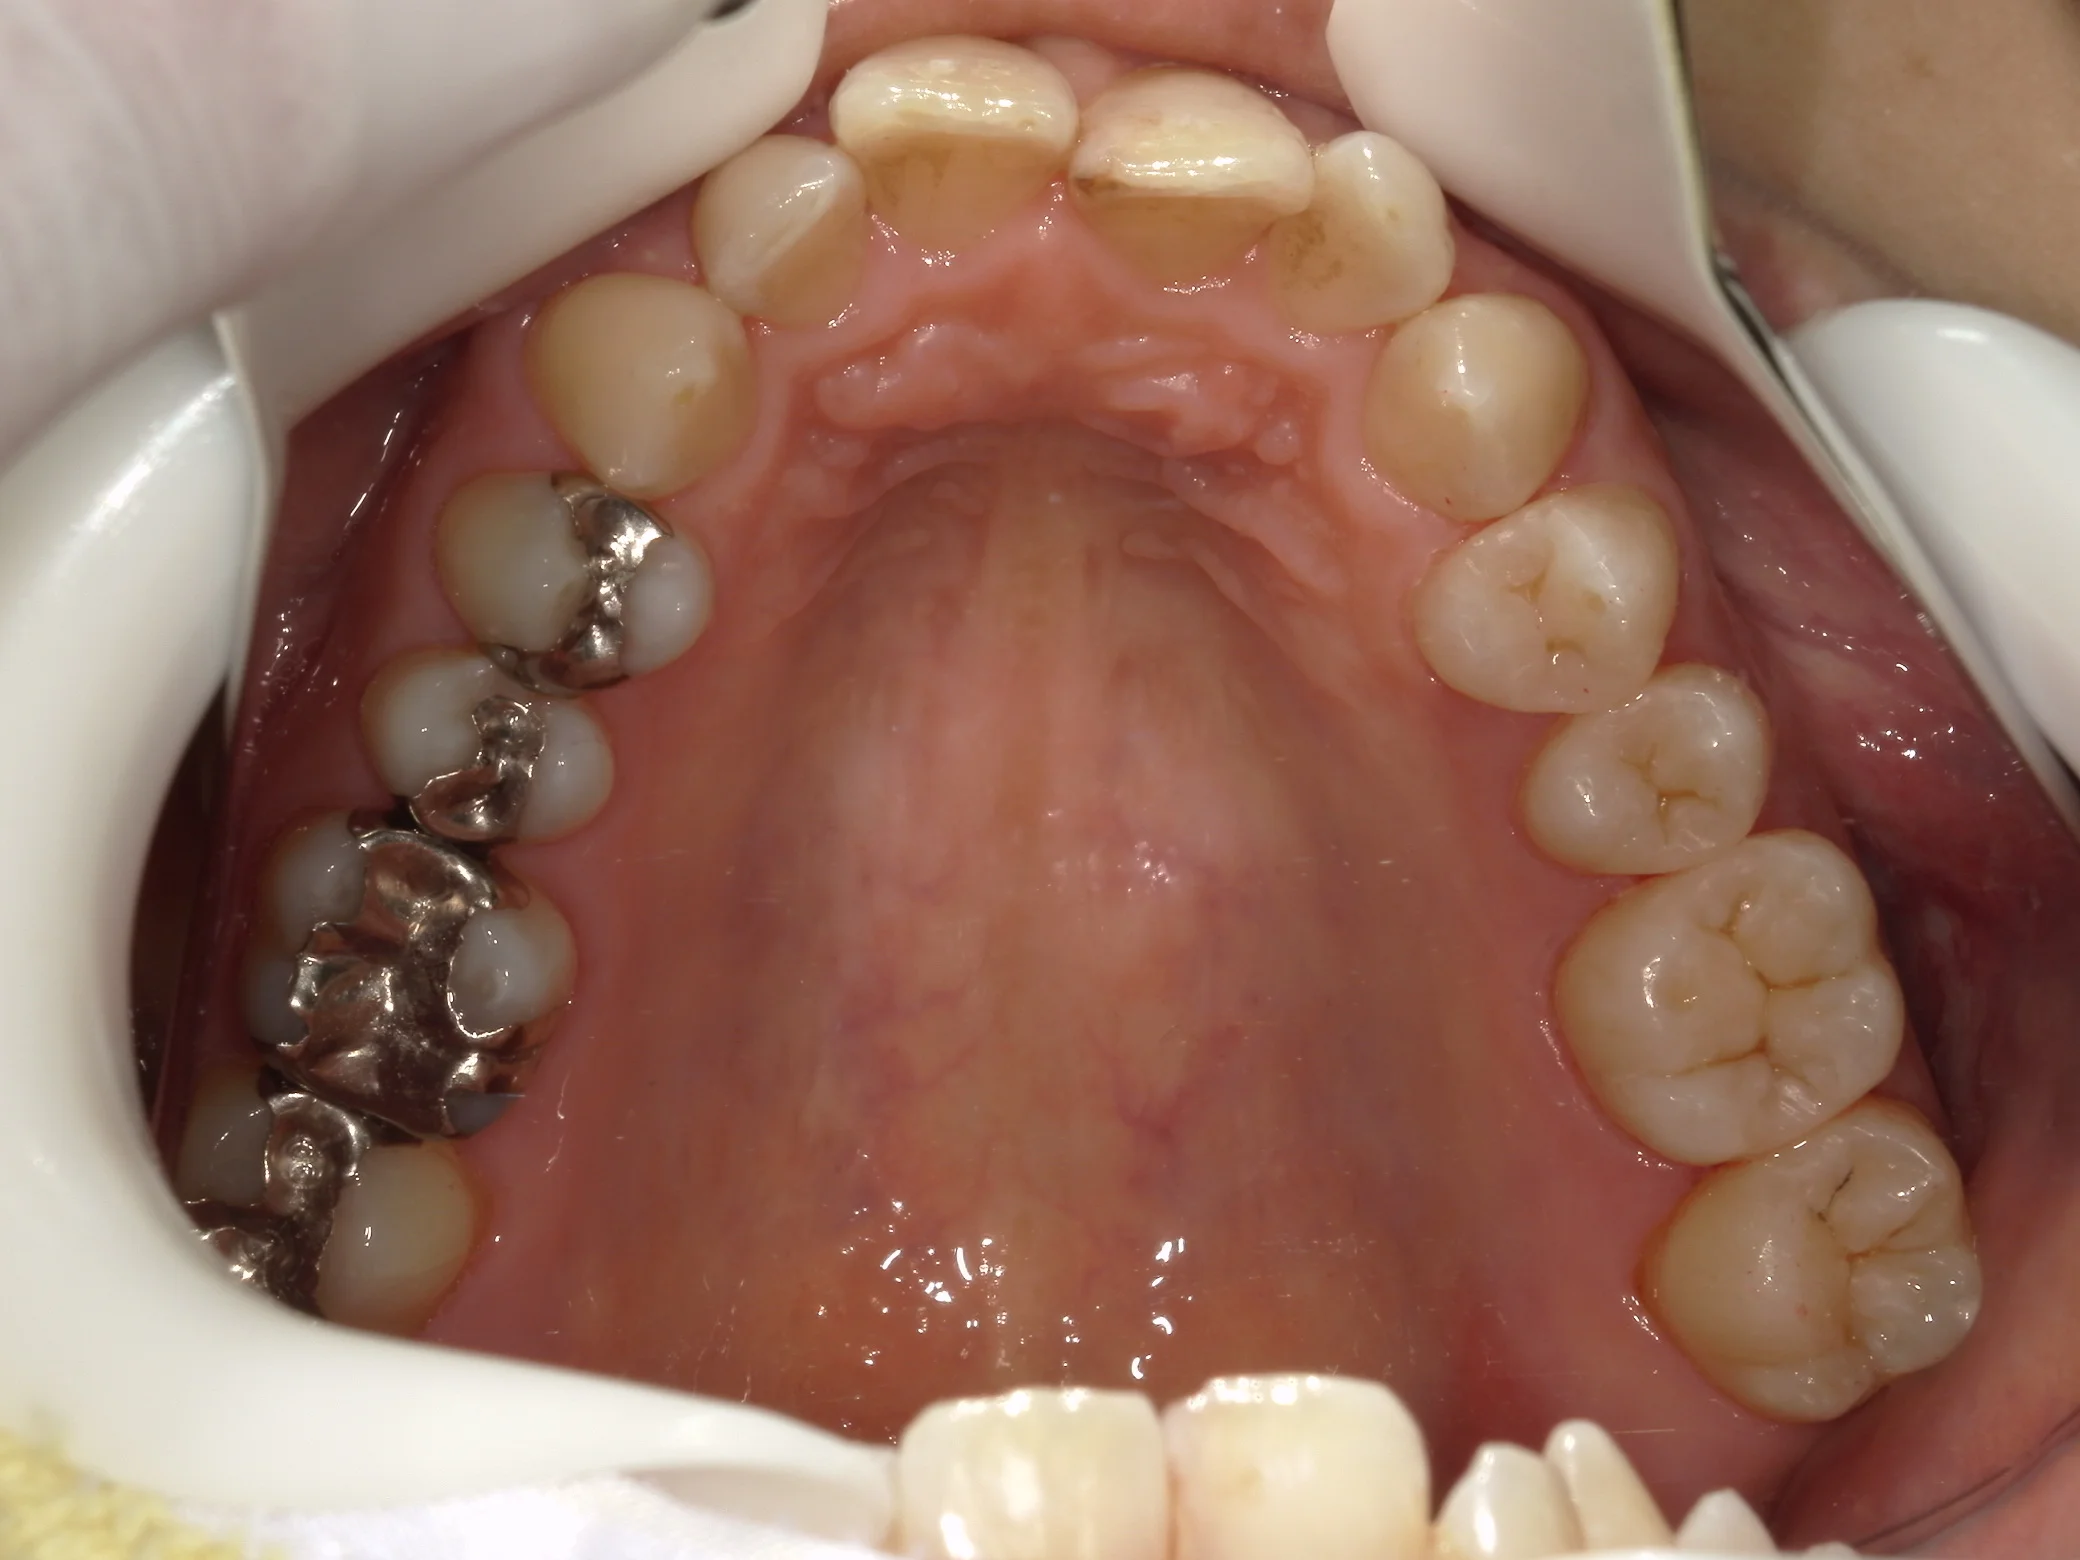

そして、別アングルからの写真がこちらです。

こちらが、術前。

こちらが術後。

随分と自然な感じに仕上げることが出来たと思います!